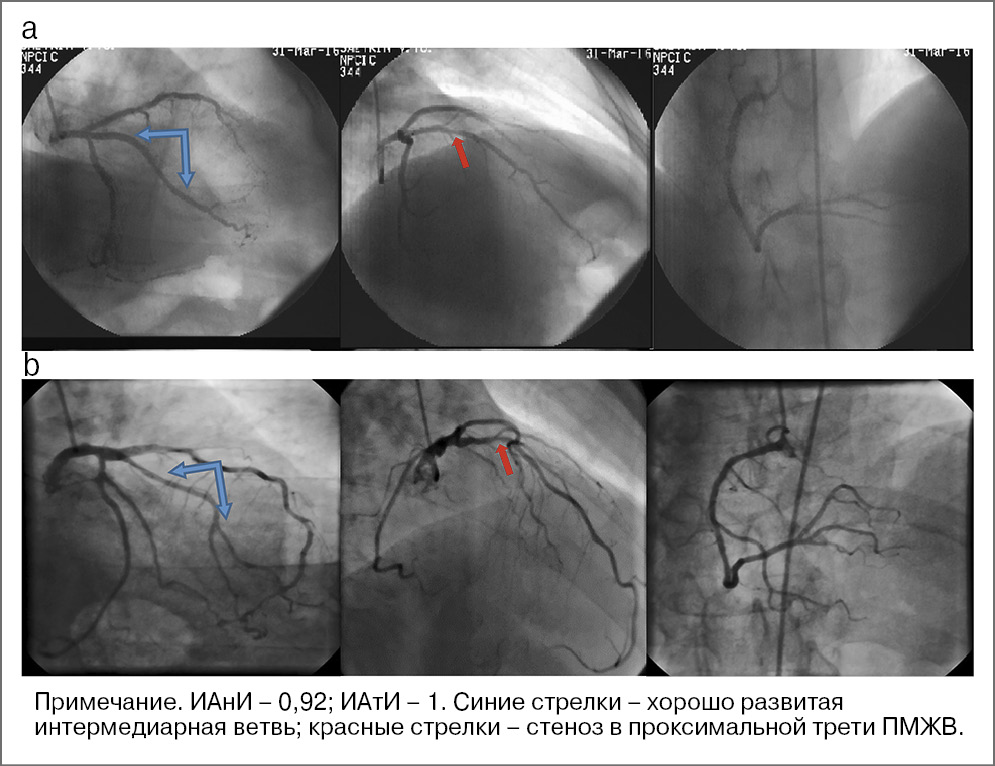

Средний показатель ИАнИ (табл. 2) в парах родных братьев составил 0,92 (0,88–0,96), что достоверно больше данного показателя в контрольных парах, сформированных из старших братьев и контрольных младших пациентов (0,88 [0, 8–0, 92], p=0,008). Эти результаты подтверждают высокую анатомическую идентичность (по геометрии сегментов, по наличию и количеству боковых ветвей) в парах сибсов (рис. 1). Более того, ИАтИ значимо выше при сравнении пар сибсов, чем при сравнении контрольных пар (Me 0,92 [0, 88–0, 92] и 0,76 [0, 72–0, 8] соответственно), с большей доказанной достоверностью (p<0,001).

Рис. 1. Сравнение коронарографий пары сибсов: a – старший брат; b – младший брат.

Высокий показатель ИАтИ в парах братьев указывает на высокую идентичность поражений коронарных артерий в исследуемой группе. Подробный анализ локализации коронарного атеросклероза в парах сибсов позволил нам определить сегменты коронарного русла, в которых атеросклеротический процесс имеет максимально высокую наследственную детерминанту.